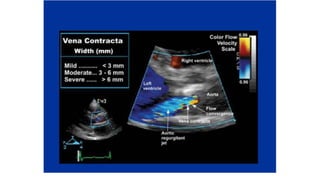

• Transthoracic echocardiography with Doppler colorflow is the most useful tool for the diagnosis of AR.

• The jet width and vena contracta width on Doppler color-flow are used to qualitatively assess the severity of

AR, whereas the regurgitant volume, regurgitant fraction, and regurgitant orifice area are used for the

quantitative assessment.

DIAGNOSTIC CRITERIA • Transthoracicechocardiography with Doppler colorflow is the most useful tool for the diagnosis of AR. • The jet width and vena contracta width on Doppler color-flow are used to qualitatively assess the severity of AR, whereas the regurgitant volume, regurgitant fraction, and regurgitant orifice area are used for the quantitative assessment.